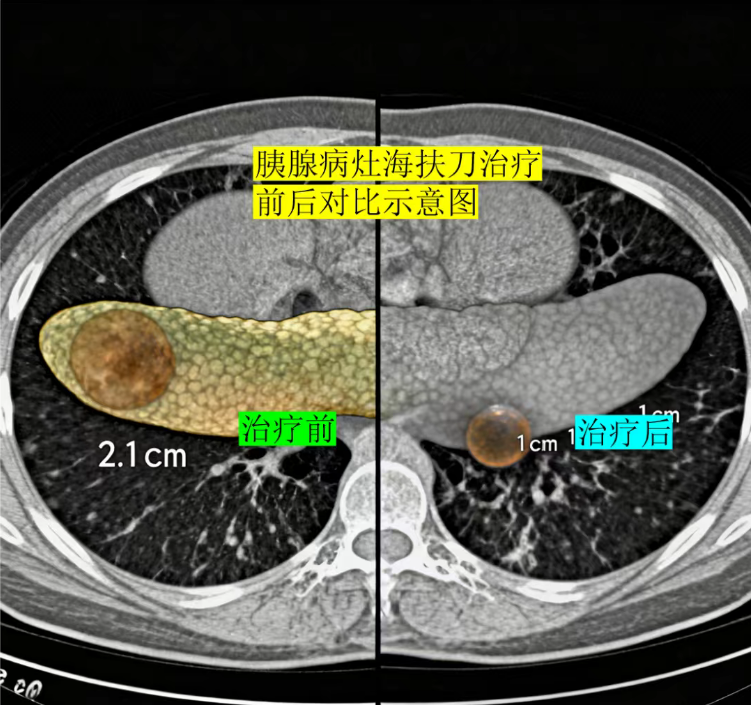

如今,距离海扶刀进行治疗已过去 4 个月,张先生复查时的结果让医患双方都倍感欣慰:术前 2.4 厘米的胰腺 IPMN 病灶,已缩小至 1 厘米左右,体积足足缩小了 80% ,且肿瘤标志物水平恢复正常,生活质量与治疗前毫无差别。